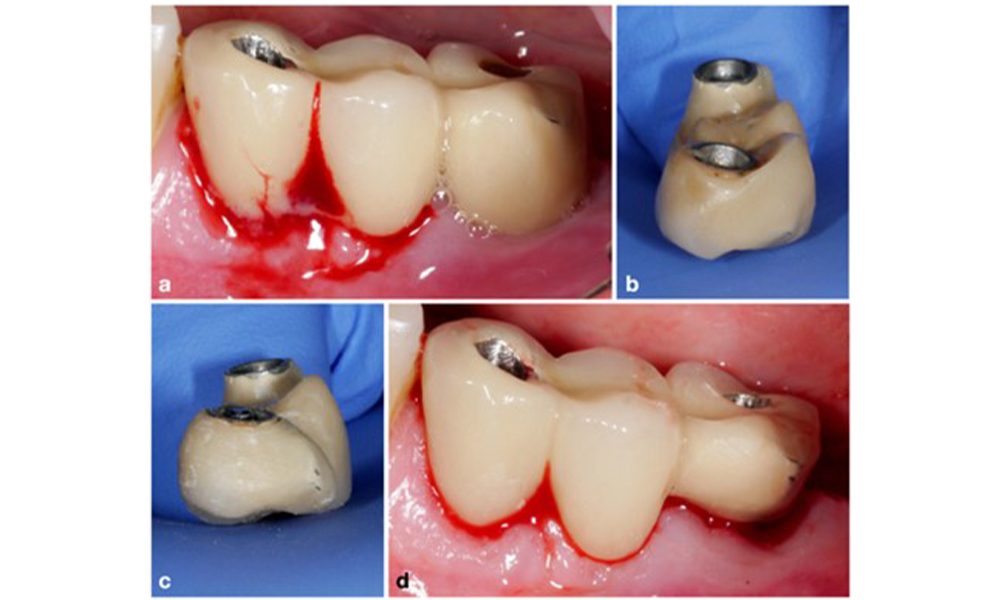

Defect extent, implant position, and its strategic importance determine whether an implant can or should be treated. Similar to a non-treatable (hopeless) implant, a severely affected implant in a multiple-unit restoration may be irrelevant for treatment, as its loss does not compromise the prosthetic restoration. Consequently, it is advisable to consider explantation either upon diagnosis or during surgical intervention (figure 8).

The prosthetic restoration should be removed during both non-surgical and surgical treatment to improve access to the implant surface. The choice of surgical intervention (e.g., resective, reconstructive, or combined) depends on several factors: (1) defect morphology (e.g., horizontal, dehiscence, intra-osseous, or combined) (figure 10), (2) implant surface (i.e., turned or modified/”rough”), and (3) presence or absence of sufficient keratinised and attached mucosa.